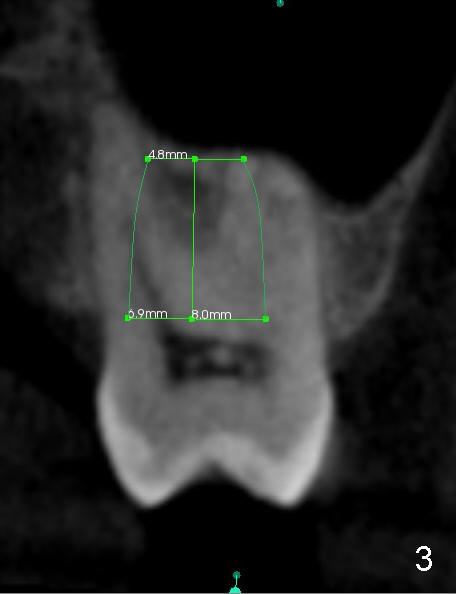

When the buccal roots are fused, there are 3 potential sites for immediate implant (Fig.1'): septum (*), buccal (B) and palatal (P) sockets. Septal placement (6.9x8 mm bone level implant) is the most ideal for restoration (Fig.3). The length of the implant can be increased (10 mm) with sinus lift so that the base of the implant between the buccal and palatal apices in height (Fig.4). Primary stability is derived mainly from the implant body engagement into the septum (Fig.5 coronal section through the septum). If bone density in the septum is high, a small implant may be appropriate (Fig.6,7: 6.4x8 mm). The large implant (6.9 mm) is chosen so that amount of bone graft to be used (Fig.8 red circles) is less.